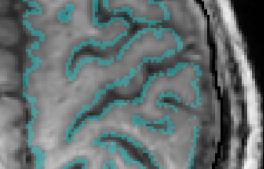

Description: Freesurfer is an open source software suite for processing and analyzing (human) brain MRI images. In the recent years, it was further optimized for ultra-high-resolution data. In the field of layer-fMRI it is the most often applied software package.

Disadvantage: It takes quite some time. Some people say it would have a rigid data organization. As a user, it’s not so straight forward to adapt/understand the algorithms and/or build your own tools. It requires a whole brain coverage, while there is not whole brain layer-fMRI acquisition protocol out there (yet). It is not straightforward to manually correct segmentation errors with a sub-voxel accuracy.

I ended up not using it because I found it very hard to include manual corrections in the segmentation. It never works perfectly (especially in M1) and manual corrections can only be made on an integer voxel level. Dependent on the brain area segmentation does not always work perfectly (like in all software packages) and manual corrections are inevitable.

Freesurfer does the layering based on the WM/GM surface. This results in larger errors and non-linearities towards the cortical surface.

The mesh density at the surface is very irregular and often less than the voxel size, this means that it misses many voxels.